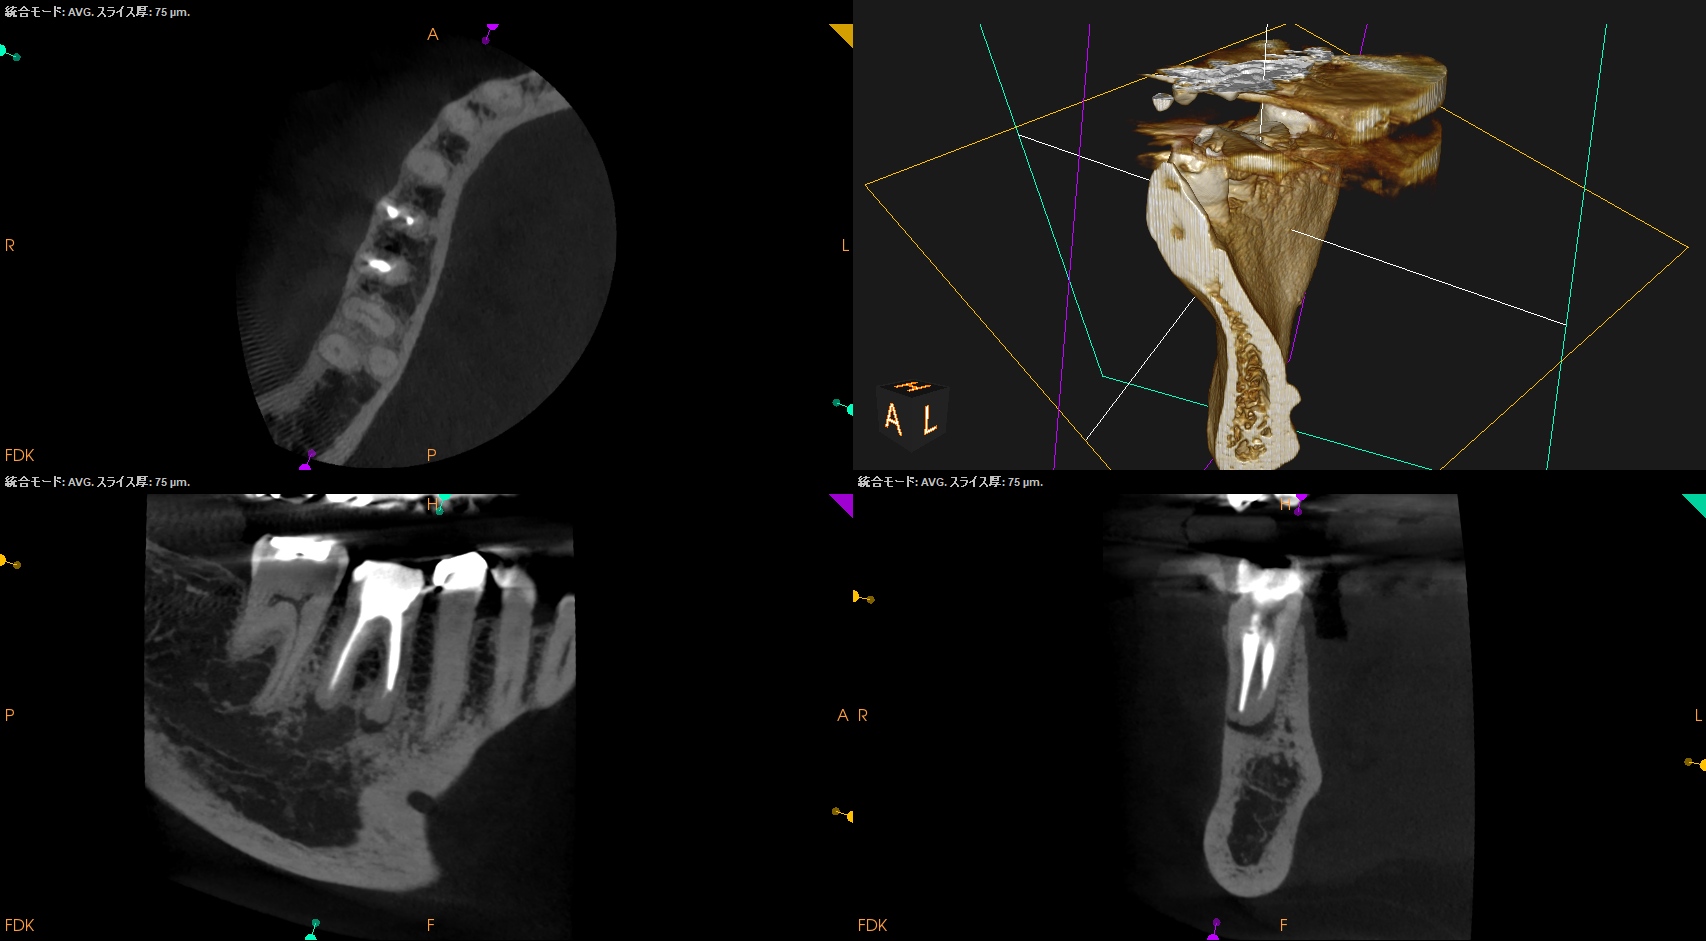

術後にPA, CBCTを撮影した。

M

D

縫合して終了した。